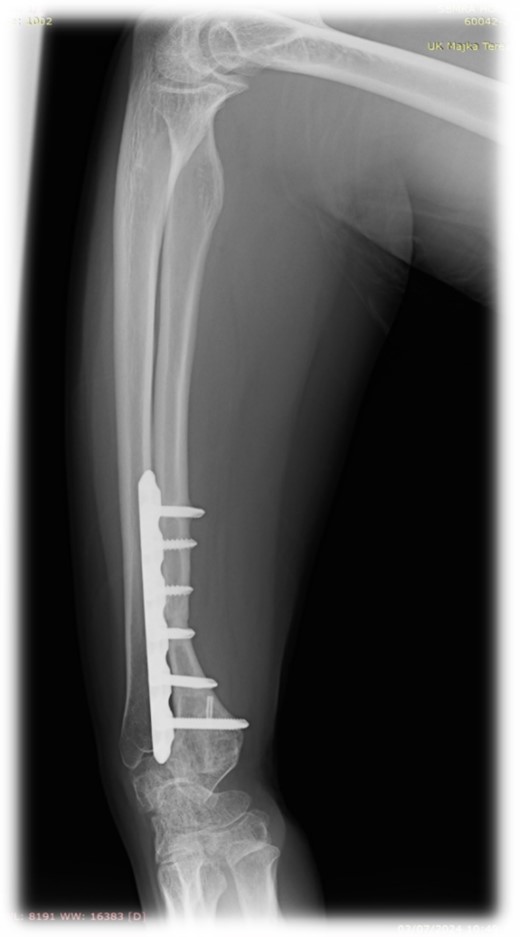

Resection of the tumor and harvesting of the bone graft from the ipsilateral proximal fibula was done simultaneously. We harvested a graft with a length of 8 cm with an inferior lateral geniculate branch and peroneal vessels to be used in the reconstruction of the defect that remained after the resection of the tumor (Fig. 2). After placing the graft in the place of the defect, the inferior lateral geniculate branch was anastomosed through a terminal-lateral anastomosis with the radial artery, while the vein was connected to the cephalic vein through an end-to-end anastomosis. The graft was fixed with a plate and screws, and two Kirschner wires (Fig. 3).

At 2 years follow-up, no clinical and X-ray signs of tumor recurrence or graft resorption were detected, both X-ray and CT confirmed that bone healing has been achieved (Figs 7 and 8) On physical examination, the patient has decreased wrist dorsal and palmar flexion, all other wrist movements are in normal range of motion and without pain (Fig. 9).

Follow-up X-ray of the right forearm 2 years after the surgery in profile plane

Follow-up X-ray of the right forearm 2 years after the surgery in anterior–posterior plane.